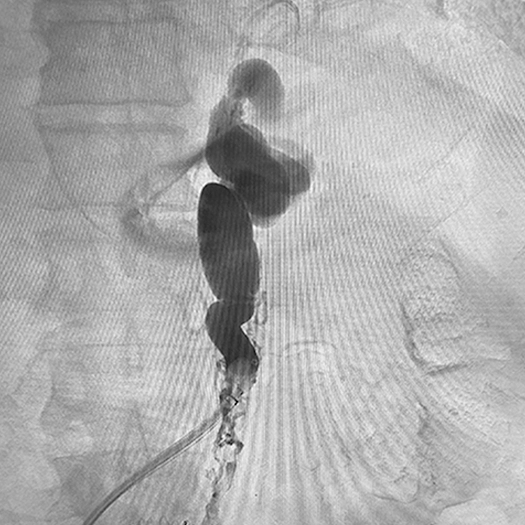

Gastric Varices Embolization

Ruby® Coil Dr. Mamdouh Khayat Vive Vascular, OH